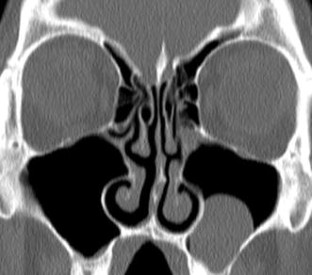

Radiological imaging of inflammatory lesions in the nasal cavity and paranasal sinuses

Paranasal sinus development and pneumatisation variants are described, and rhinosinusitis and different patterns of inflammatory sinonasal diseases are reviewed. Other inflammatory sinonasal diseases, e.g., fungal sinusitis, mucocele, pyocele and sinonasal manifestations in systemic diseases, are briefly described. Computed tomography (CT) is the primary modality in diagnosing and mapping suspected inflammatory sinonasal disease. Magnetic resonance (MR) imaging is complementary to CT if fungal sinusitis, pyocele or malignancy are suspected.